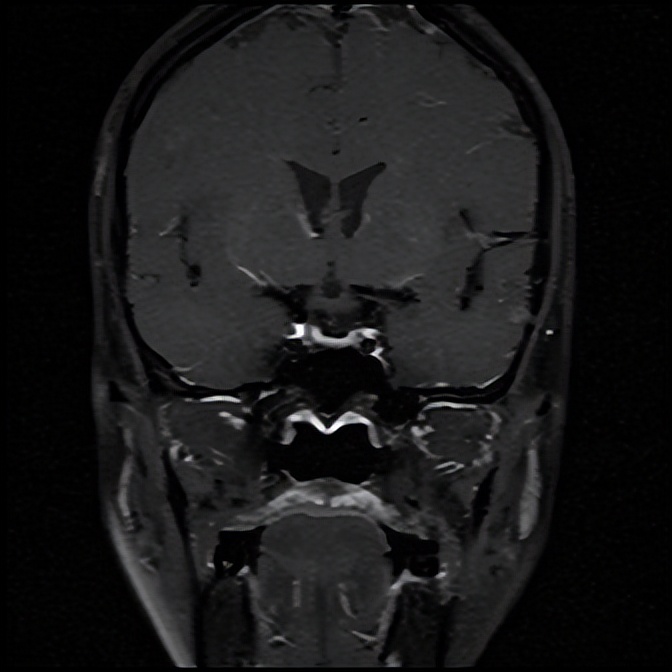

住院期间,银主任经过详细的询问病史和查体,为王女士有针对性地完善了相关检验、检查,入院急查血钠107.0mmol/L,血氯76.0mmol/L(参考范围96-108mmol/L),经积极补钠、护胃及对症支持治疗后王女士的血钠稳步上升,症状逐渐减轻,相关结果回报上午皮质醇、促肾上腺皮质激素(ACTH)水平降低,垂体磁共振未见明显异常。会不会是内分泌方面的因素导致低钠血症呢?深圳大学总医院内分泌代谢病科派驻罗城县人民医院内四科的丘雅维主治医师应邀会诊。丘医生分析患者体型消瘦,皮肤黏膜无明显色素沉着,低血压,轻度贫血,白细胞及中性粒细胞、血糖和糖化血红蛋白均偏低、低钠低氯、上午皮质醇和ACTH水平降低,初步考虑继发性肾上腺皮质功能减退可能性大,并对患者垂体磁共振再次阅片,发现垂体组织受压变扁,表现为部分性空泡蝶鞍。请深圳大学总医院影像科派驻罗城县人民医院影像科的杨智钧主治医师阅片后也支持部分性空泡蝶鞍的影像学诊断。

注:箭头所指为受压变扁的垂体。

那么什么叫空泡蝶鞍呢?所谓空泡蝶鞍综合征,是因鞍膈缺损或垂体萎缩,蛛网膜下腔在脑脊液压力下疝入鞍内,其中脑脊液填充,致蝶鞍扩大变形,垂体受压变平而产生的一系列临床变现,患者可出现头痛、视野缺损、垂体功能异常等表现。而垂体功能异常可显现为一种或多种垂体相关激素水平异常,如影响到肾上腺皮质轴导致肾上腺皮质功能减退,患者可出现头晕、血压降低、食欲减退、恶心呕吐、疲乏无力、消瘦、低血糖、低血钠等表现。